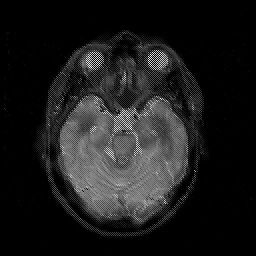

Glioblastoma multiforme overlay -- Slice #20

[Home][Help][Clinical][Tour 1][Tour 2][Tour 3] Slice 20